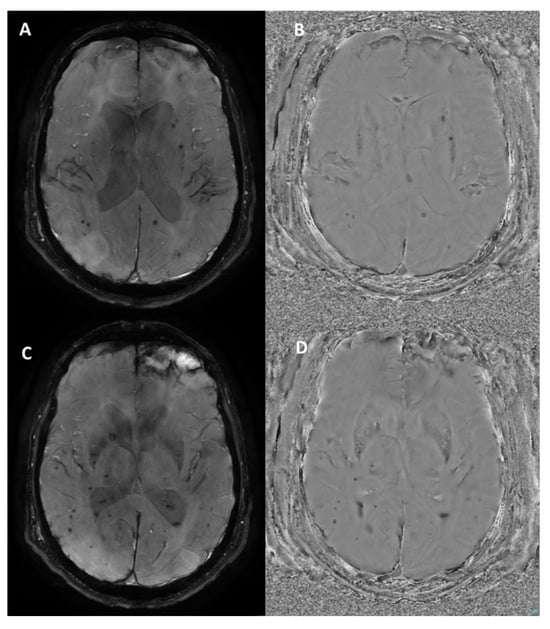

4.2. Multiple Sclerosis

- Maggi, P.; Sati, P.; Nair, G.; Cortese, I.C.M.; Jacobson, S.; Smith, B.R.; Nath, A.; Ohayon, J.; van Pesch, V.; Perrotta, G.; et al. Paramagnetic Rim Lesions are Specific to Multiple Sclerosis: An International Multicenter 3T MRI Study. Ann. Neurol. 2020, 88, 1034–1042. [Google Scholar] [CrossRef]

- Meaton, I.; Altokhis, A.; Allen, C.M.; A Clarke, M.; Sinnecker, T.; Meier, D.; Enzinger, C.; Calabrese, M.; De Stefano, N.; Pitiot, A.; et al. Paramagnetic rims are a promising diagnostic imaging biomarker in multiple sclerosis. Mult. Scler. J. 2022, 28, 2212–2220. [Google Scholar] [CrossRef]